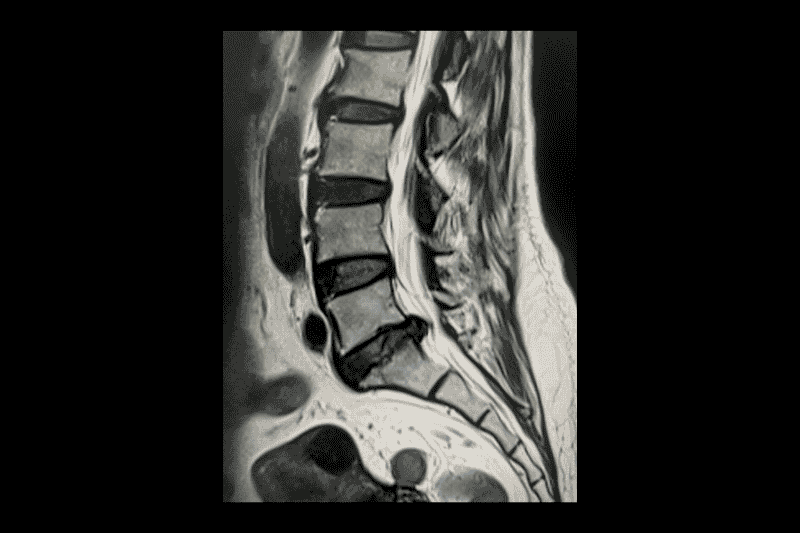

หมอนรองกระดูกกดทับเส้นประสาท

หมอนรองกระดูกกดทับเส้นประสาท หรือที่หลายคนเรียกว่า “หมอนรองกระดูกทับเส้น” เป็นภาวะที่ หมอนรองกระดูกสันหลัง เกิดการเสื่อมหรือเคลื่อนที่ผิดตำแหน่ง ทำให้ไปกดทับ เส้นประสาท

หมอนรองกระดูกทับเส้นประสาทกับกระดูกพรุนต่างกันอย่างไร

หมอนรองกระดูกทับเส้นประสาทและกระดูกพรุนเป็นปัญหาสุขภาพที่เกี่ยวข้องกับระบบกระดูกและข้อ แต่แม้จะเกิดในบริเวณคล้ายกัน เช่น กระดูกสันหลังหรือหลังส่วนล่าง